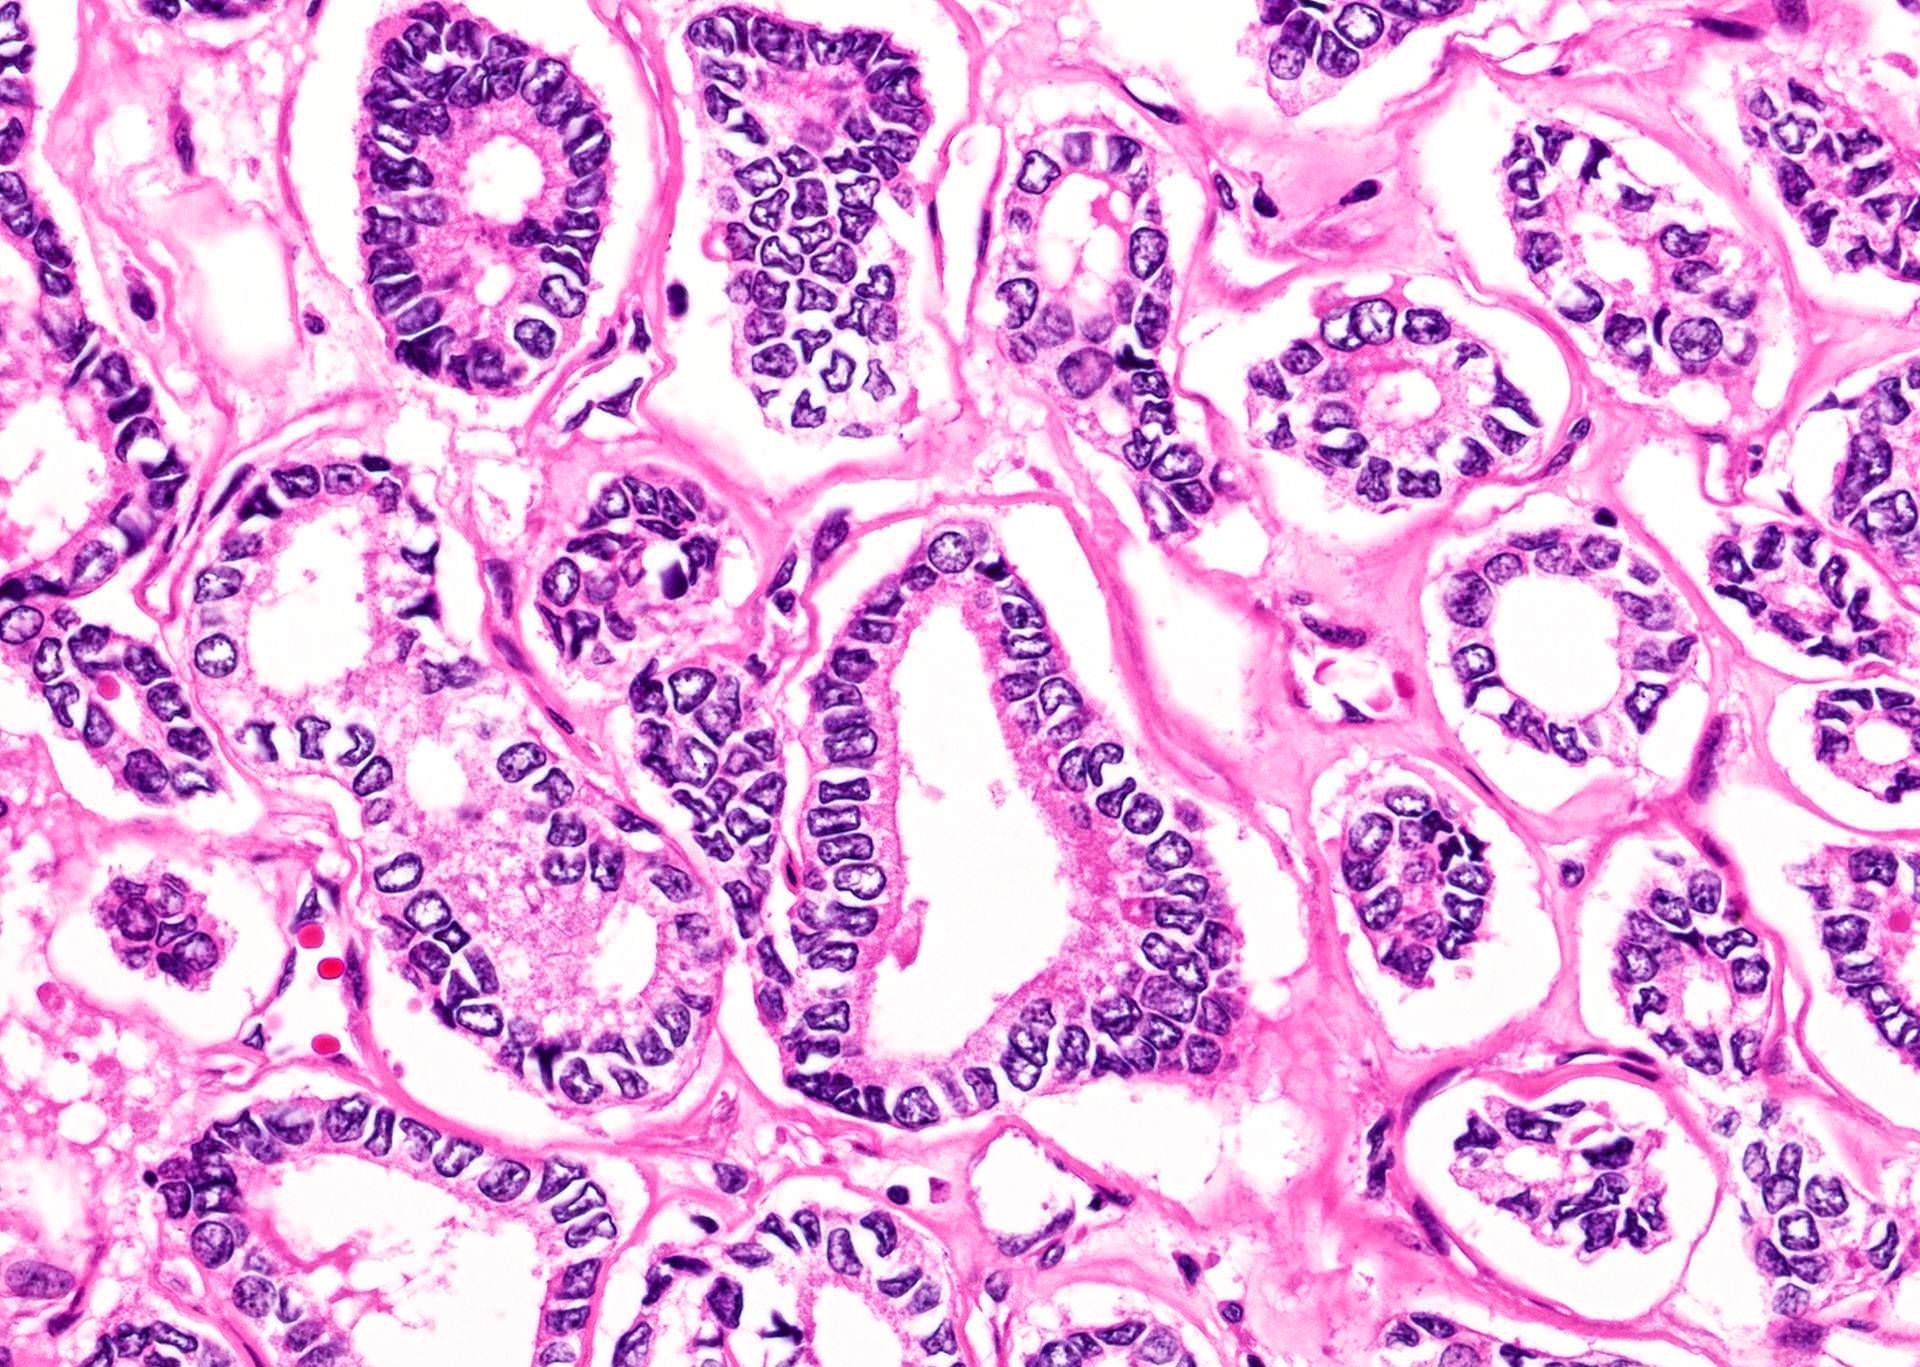

Microscopic (histologic) description

- Nuclear features:

- Change of nuclear size and shape: nuclear enlargement, elongation and overlapping

- Chromatin characteristics: chromatin clearing / optically clear chromatin, chromatin margination, glassy / ground glass nuclei, Orphan Annie nuclei

- Nuclear membrane irregularity: irregular nuclear contour, nuclear grooves and nuclear pseudoinclusions (represent cytoplasmic invaginations)

- Variants:

- Classic: complex, branching, randomly oriented papillae with fibrovascular cores

- Tumors with both papillary and follicular architecture should be classified as classic variant, given the associated risk of nodal metastasis (Thyroid 2019;29:1792)

- Follicular: neoplastic cells arranged as macro or microfollicles with central colloid

- Colloid is usually dense and hypereosinophilic (inspissated colloid)

- Psammoma bodies defined as laminated microcalcification are frequently associated with classic, tall cell, hobnail and diffuse sclerosing variants; it is postulated that psammoma bodies are formed in the hyalinized core / stalk of papillae

Microscopic (histologic) images

Contributed by Andrey Bychkov, M.D., Ph.D.

Nuclear features